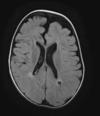

46 anos, pós trauma

Lesão axonal difusa A TC mostra discreta HSA RM T2 \* mostra focos de hemossiderina na transição substância branca e cinzenta, consistentes com LAD. Observe que a localização das microbleeds é diferente dos sangramentos CAA localizados na periferia.

FIESTA- Demonstra melhor a parede do cisto e o scolex